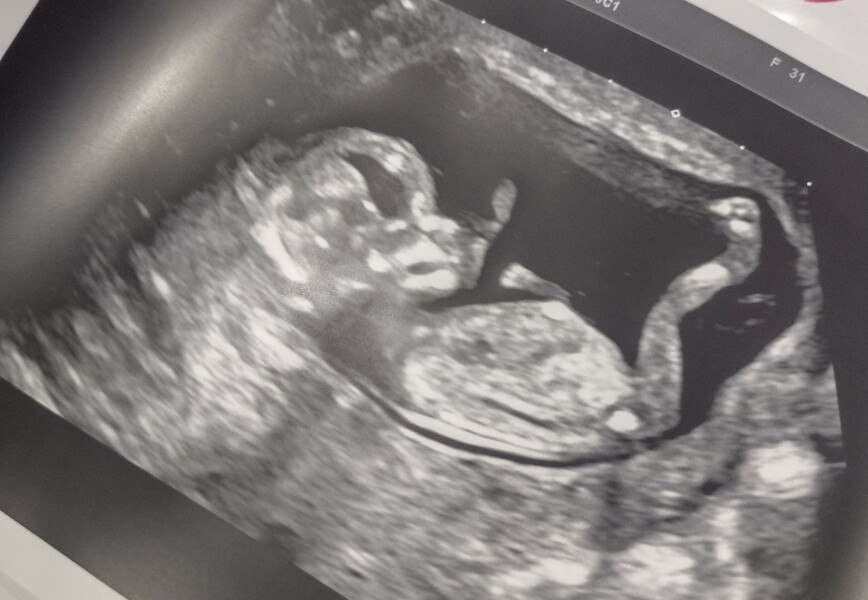

@Franklin321 gorgeous scan ❤️ as you're having a gender scan are you happy for guesses?

@TeddyBeans ooh yeh, what do you think? I’ve been studying it all afternoon 😂

@Franklin321 from the skull I'm gonna say a boy. The nub kind of hints to a girl (it's very straight) but there's still time for it to rise. The skull is very boxy which is telltale boy!

LittleAcorn20 · 05/09/2022 20:33

I am not finding out gender beforehand, waiting til the birth... But still interested to know if anyone has any theories 😁 I can't work skull theory out myself!

I see a rounded forehead = girl

But a squared off jaw = boy

🤷‍♀️

@LittleAcorn20 I'd guess boy but it could be either tbh 😂 Regardless, the legs on that baby are astounding! You have a gymnast in the making